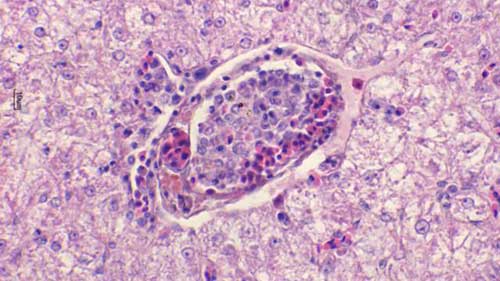

錐體蟲